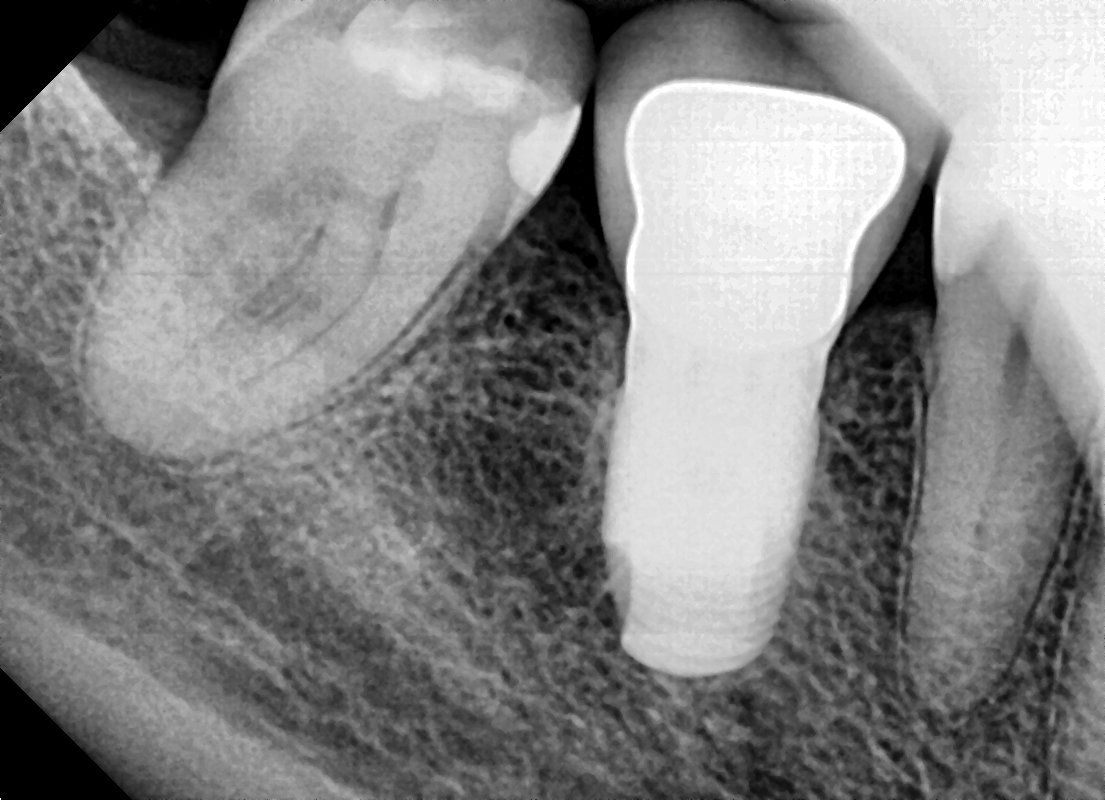

Dental implants are the modern alternative. Instead of cutting down two perfectly healthy teeth, your periodontist inserts a dental implant into the jawbone to replace your missing tooth root. As it heals, the implant becomes solidly fixed into your jawbone (a process called osseointegration). Once the implant is ready, your referring dentist then places a crown onto this dental implant that looks, feels, and functions like your natural tooth. Dental implants stand alone and do not rely on your natural teeth for support.

Dental implants are today's treatment of choice for replacing missing teeth. They are long lasting, natural in appearance, and promote jaw health. By working closely with your dentist, we hope to provide you with a functional and esthetic replacement tooth that will last for a very long time.